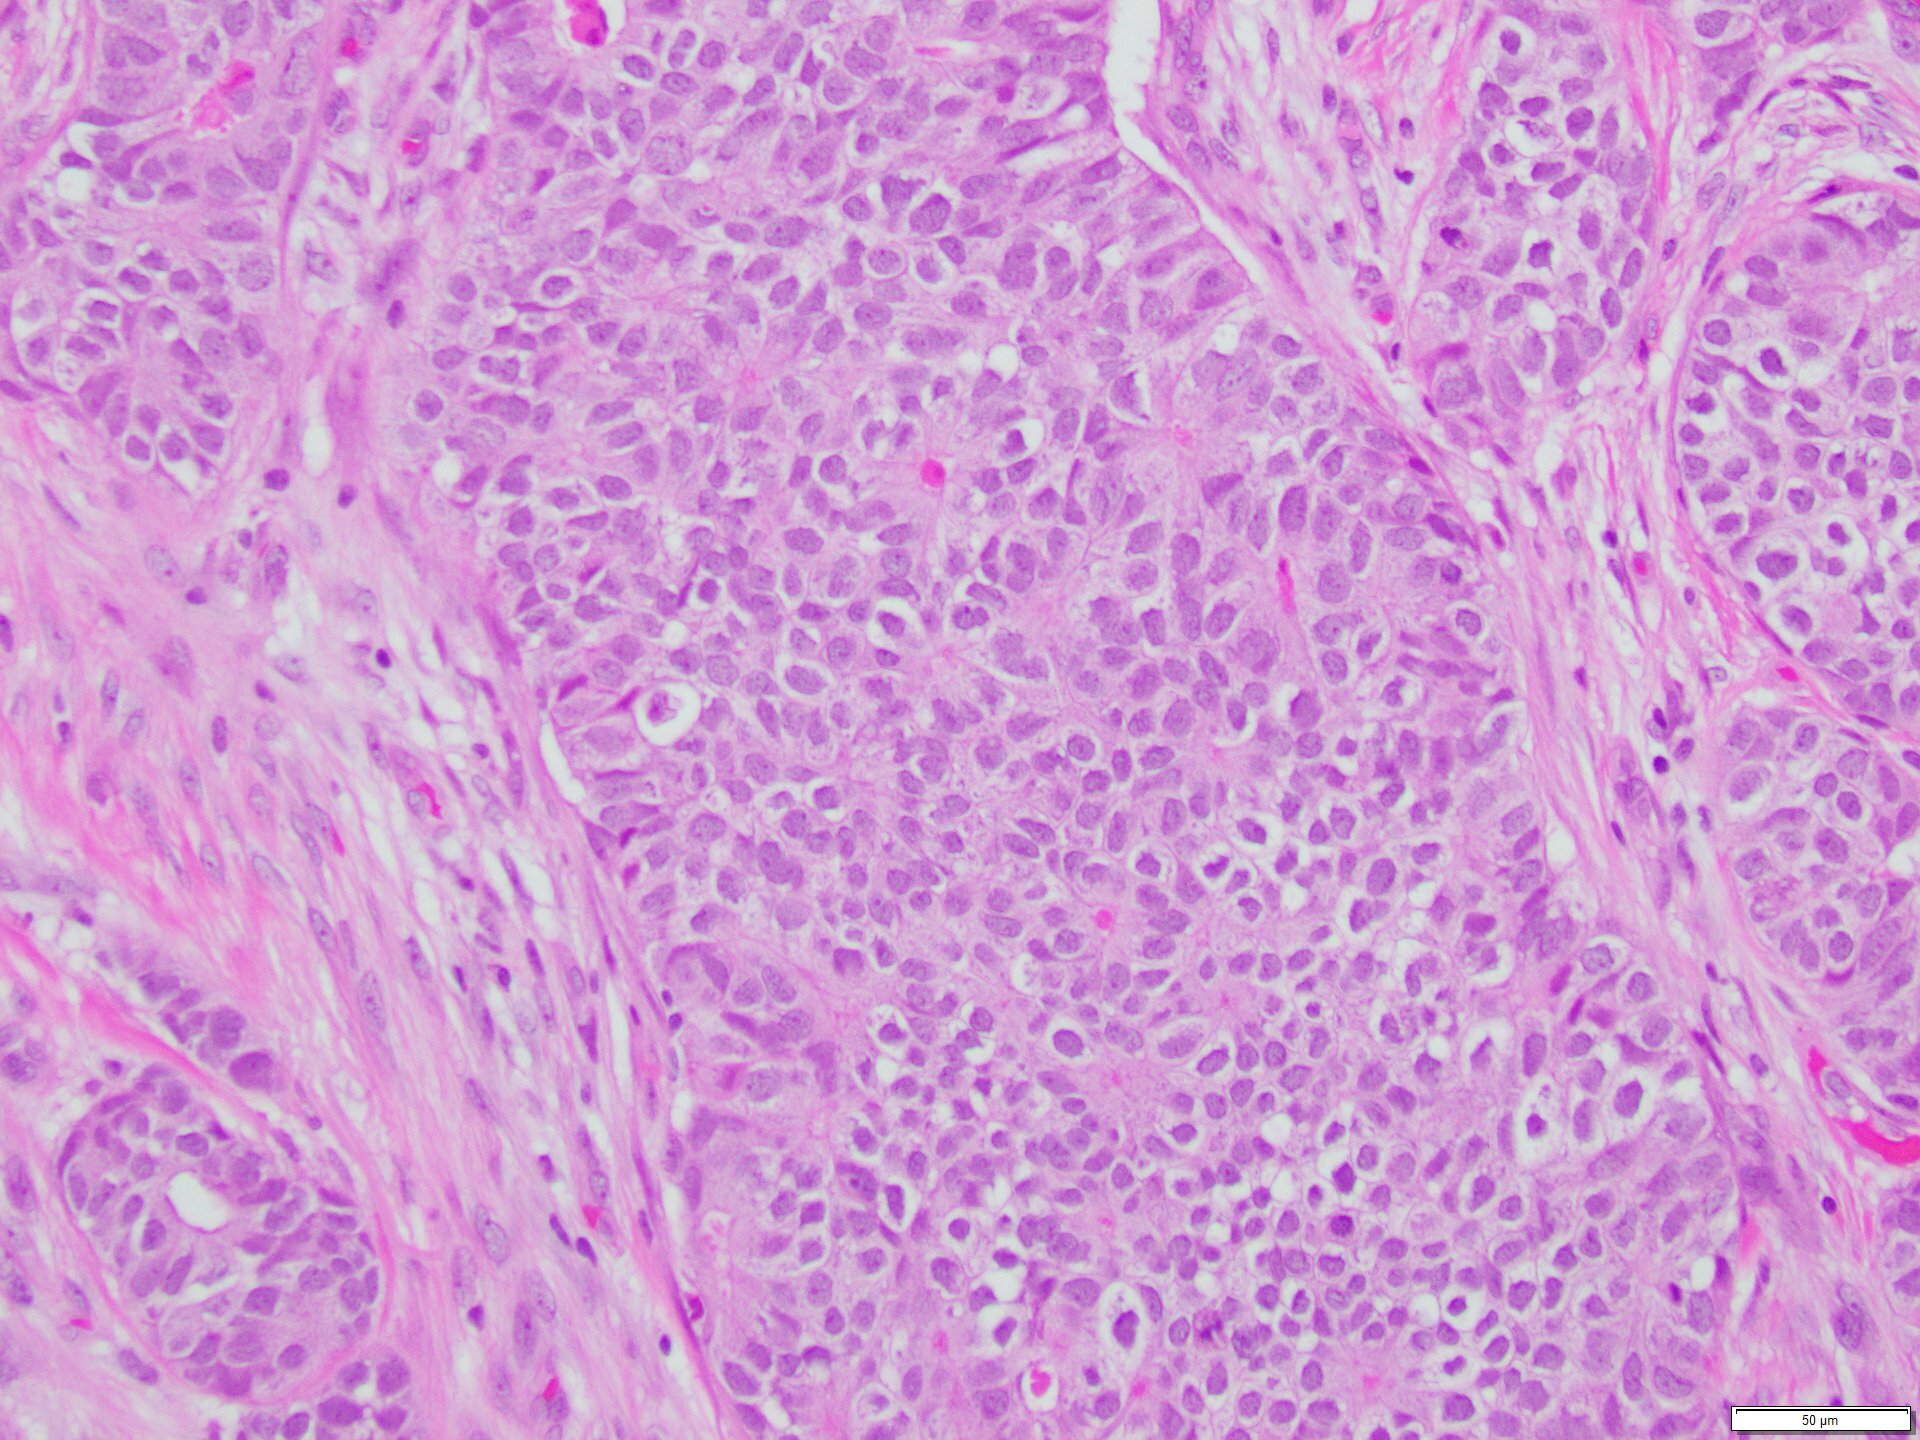

The skin lesion was completely excised and sent to pathology for diagnosis (Figures 1-3). The lesion is hypercellular with an infiltrative, predominantly solid, growth pattern in the dermis and subcutaneous tissue. It is highly vascular and has complex anastomosing and poorly formed vascular channels. The tumor cells are large, pleomorphic, have vesicular chromatin, and prominent nucleoli. There are frequent mitoses and extravasated red blood cells throughout. Immunohistochemistry shows the tumor cells are diffusely positive for ERG (Figure 4) and c-MYC (Figure 5) while negative for pan-cytokeratin (Figure 6) and GATA3. Subsequently, the patient underwent a left total mastectomy.